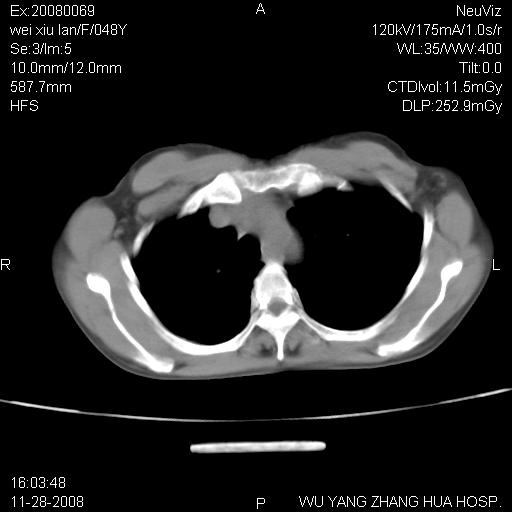

标题: CT16847:女,48岁,咳嗽,发热两日,平常偶有上腹部不适。 [打印本页]

标题: CT16847:女,48岁,咳嗽,发热两日,平常偶有上腹部不适。

能否考虑食管裂孔疝?请老师们多多指教。

这个是左侧膈膨升伴不完全性胃翻转,手术将松弛的左横膈膜折叠缝合即解决问题。

支持左侧膈疝,心脏受压右移.

胃、脾脏及部分肠管明显升高,并压迫心脏移位,

首先考虑:左侧膈疝。

左侧胸腔内见胃肠及脾脏影

支持膈疝

左膈顶及肋膈角均上移,膈面光滑,考虑左膈肌麻痹